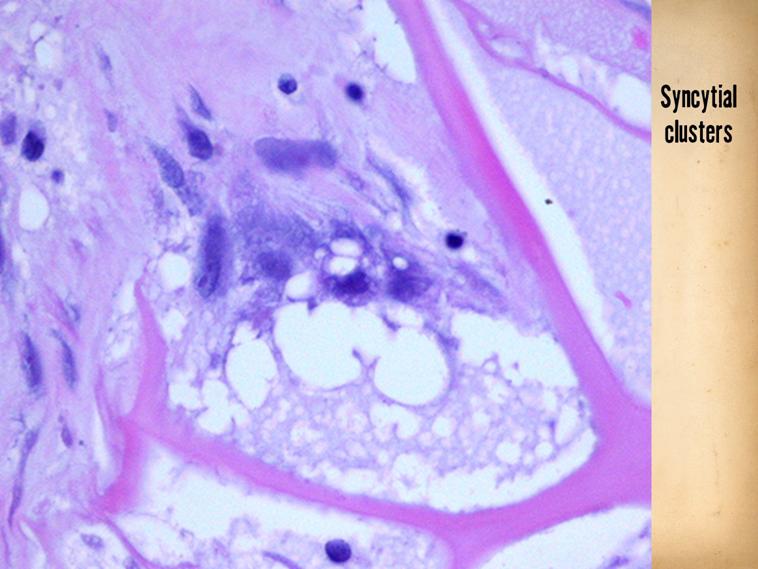

LEFT - The reasons why the material induces embryonic activities can be studied in other resources (at Arimedica.com).  This slide shows a key piece of evidence - the syncytial fibroblast, which is the embryonic dermatoblast, a cell which NEVER - not ever - appears in a normally healing wound.

SLIDE SUMMARY:  The basis for Integra CGM’s biological effects is understood in many ways.  This illustrates a key component: the matrix is developing a cluster of syncytial fibroblasts.  This is the embryonic dermatoblast, a cell which NEVER appears in normal wound post-inflammatory repair.

Here is a close up of another syncytial cluster.  The small pioneer cells, seen on the previous slide, proliferate into small clusters like this, composed of several syncytial fibroblasts. which are starting to make young fibrillar collagen (pale pink), nestled within a pore or domain of the matrix.  Some other not-yet-transformed lymphoid progenitor cells are also present (they must bind to the matrix to begin the process, an effect of the aminoglycan in the material).